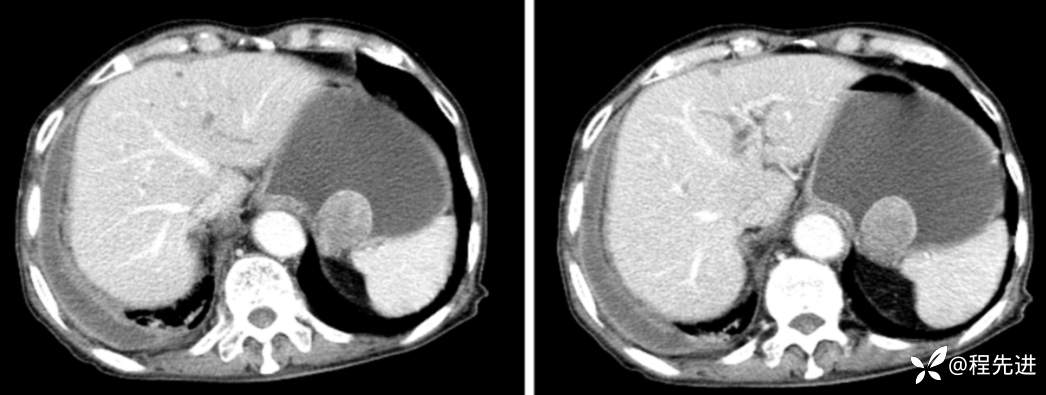

CT

平扫

动脉期